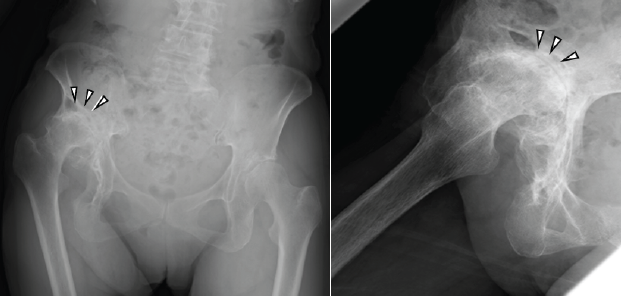

An 80-year-old woman underwent rotational acetabular osteotomy 20 years ago for right hip dysplasia and osteoarthritis. However, she experienced persistent post-operative hip pain and gradually developed severe joint contracture. At the time of presentation to our hospital, she required crutches for ambulation due to intense right hip pain. The affected limb was approximately 5 cm shorter than the contralateral side. The range of motion of the right hip was markedly restricted, with 20° flexion, 0° extension, 5° abduction, 10° adduction, 0° external rotation, and 30° internal rotation. Radiographs demonstrated that the right femoral head was deformed and dislocated proximally (Fig. 1).

Figure 1: Radiographs at the first visit (left, anteroposterior view; right, lateral view). The images reveal high dislocation of the right hip, deformity of the femoral head, and severe narrowing of the joint space (arrowheads).